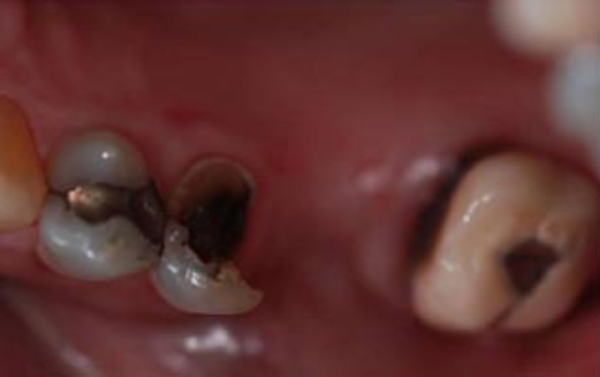

Susan was missing one tooth and the tooth beside it was broken; making shewing difficult and uncomfortable. We created a three-unity bridge to beautifully replace and repair her teeth. Now she can chew with ease – her teeth look marvelous – just the way nature intended.

Before